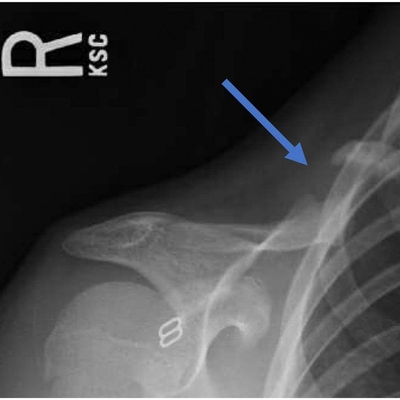

Click on an image below to view more info.